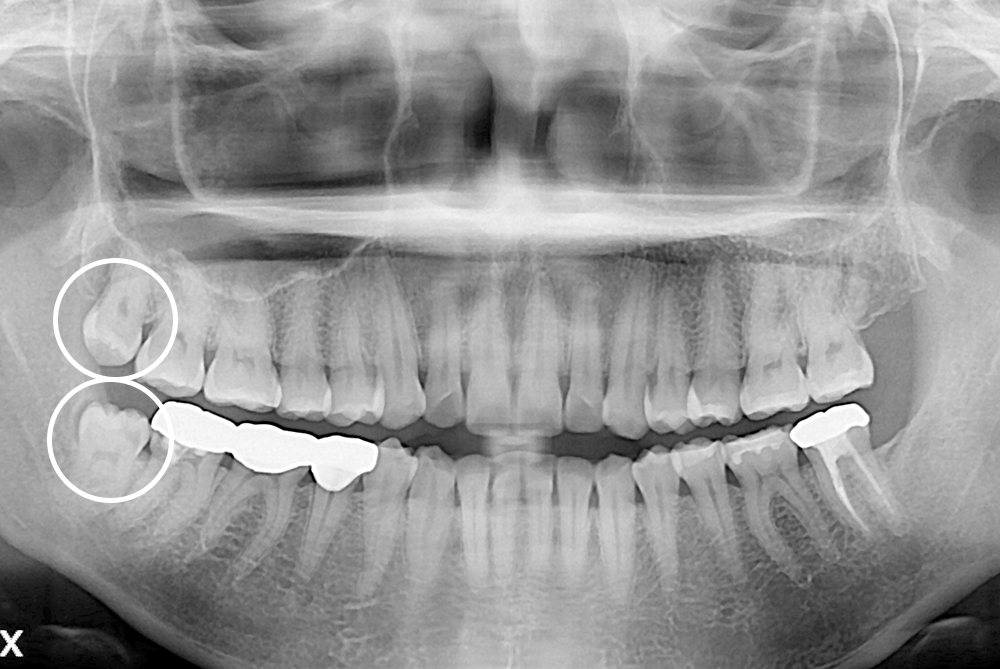

[사랑니] 매복 사랑니 발치

치료전 : 2019-02-15